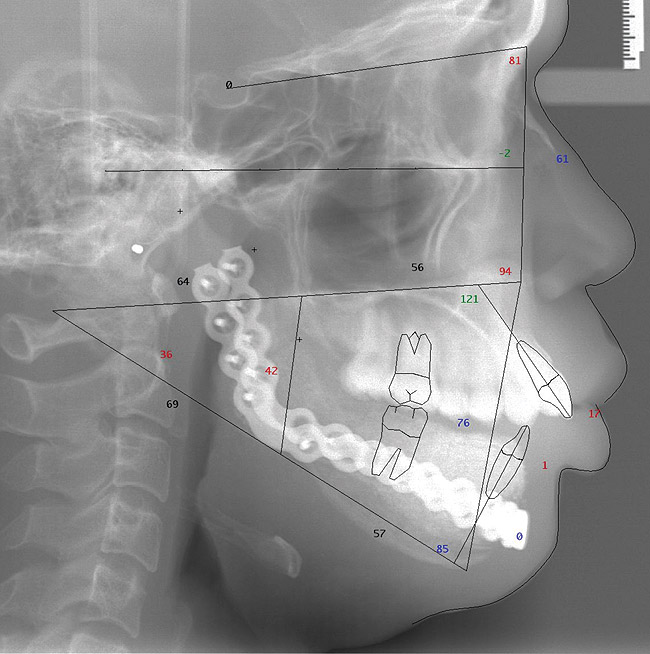

The initial intraoral photograph of the maxillary teeth showed the severity of the dental protrusion, the incisor irregularity, and a dual plane of occlusion. It was evident that the premolars and molars were extruded relative to the incisor esthetic plane (Figure 9). Orthodontic appliances were placed and the maxillary left and right first bicuspids extracted. To establish adequate posterior anchorage for the incisor retraction and the molar intrusion that would be necessary, a 1.6 mm x 8 mm temporary anchorage device (TAD) was placed bilaterally in the buccal-attached gingiva between the roots of the first and second molars.10,11 Care was taken to avoid contact with and not abrade the cementum in this interradicular area.12 Nickel titanium 12-mm closed coils were attached from each TAD to the orthodontic arch wire directly between the lateral incisors and canines (Figure 10). The unique mechanical properties of superelasticity and shape memory exhibited by nickel titanium supplied the constant physiologic force necessary for en masse anterior tooth movement.13 The maxillary incisors were placed in the desired axial and anteroposterior position that would be consistent with the axial placement of the endosseous dental implants in the anterior reconstructed mandible (Figure 11). By these movements, the esthetic occlusal plane and incisor display were established.

Figure 9  Dental protrusion with incisor irregularity and a dual plane of occlusion.

Figure 9

Figure 10  Nickel titanium coils were attached to TADs for incisor movement.

Figure 10